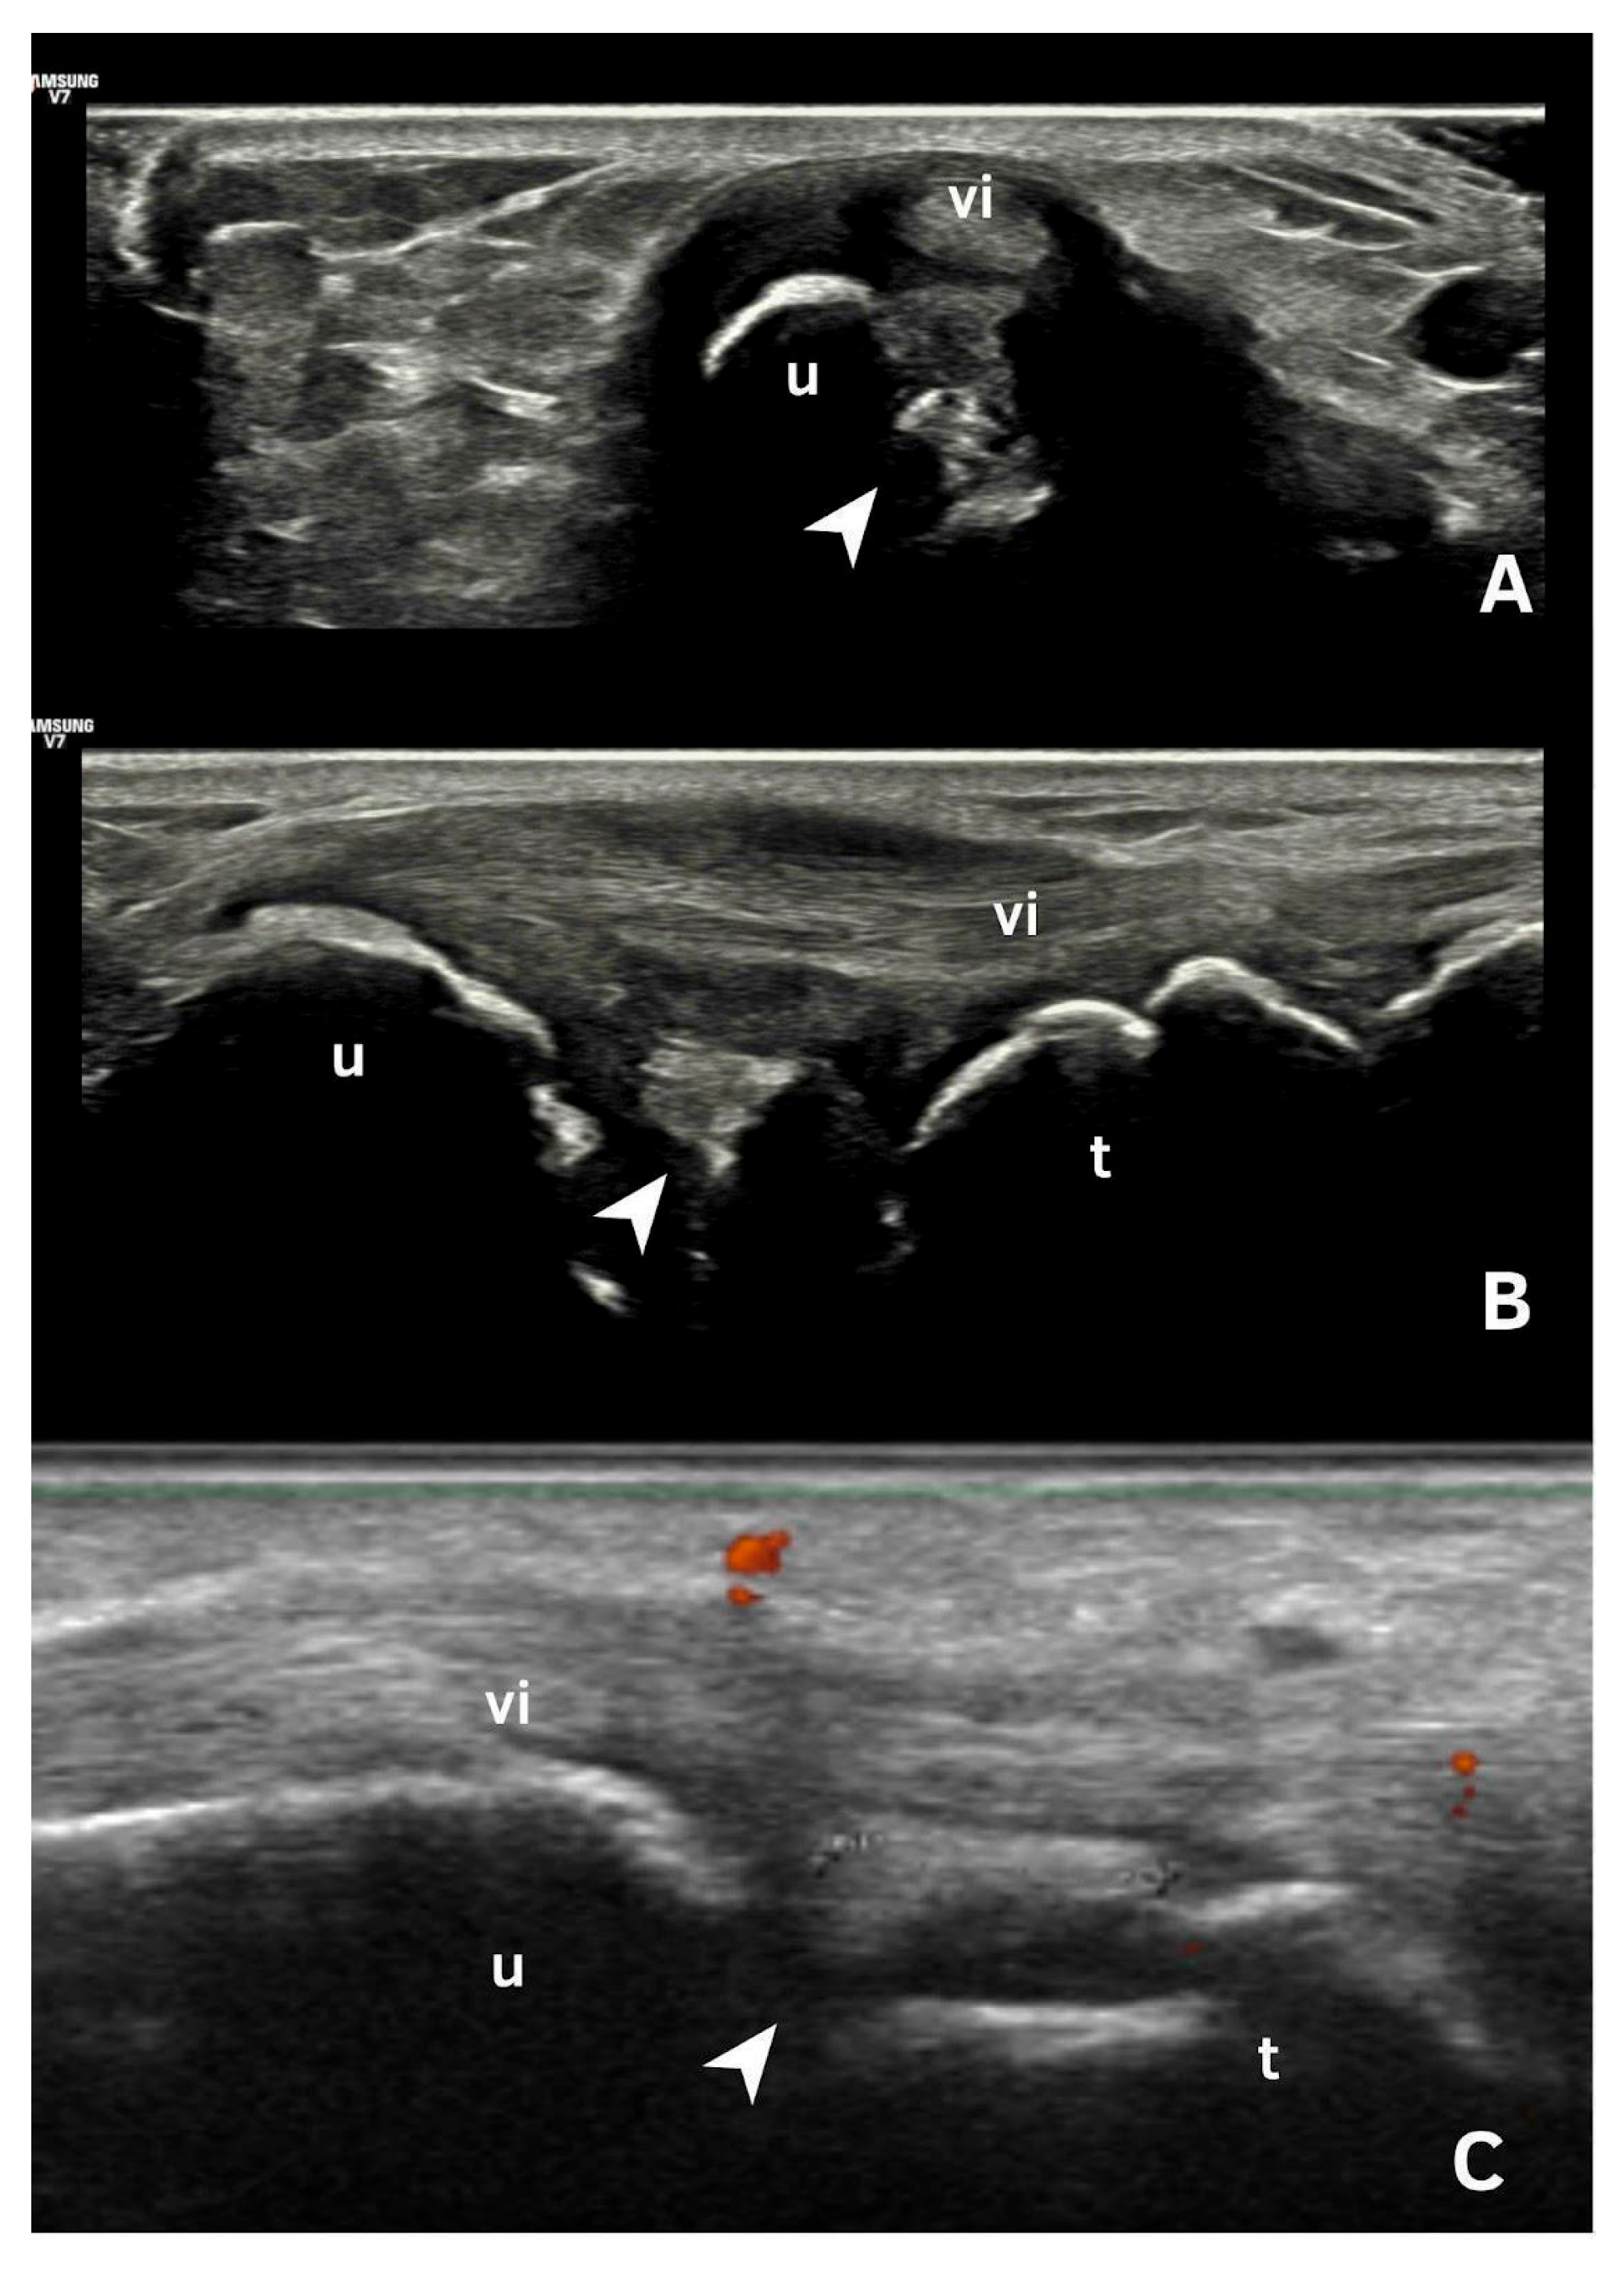

| Pseudo-double contour sign | Shape: Deposits of variable shape. Echogenicity: Hyperechoic, without posterior shadowing. Localization: Localized at the chondro-synovial interface or in the joint capsule and adjacent ligaments. Dynamic scanning: Moves in the opposite direction of cartilage and adjacent bone. Examples: Knee, proximal, and distal radio-ulnar joint. |